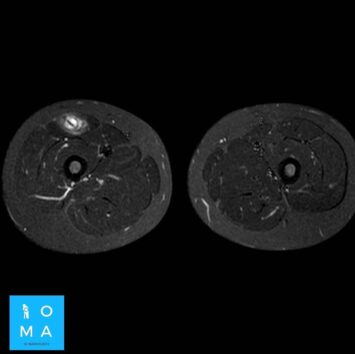

.La sintomatología es poco clara, la RMN aporta información fundamental acerca de la extensión y localización (lesiones cercanas a la inserción requieren mas días de tratamiento) , sin embargo el edema sobredimenciona la lesión, por lo que el método de elección, para clasificar el grado, es la ecografía realizada por un especialista en aparato osteomioarticular.